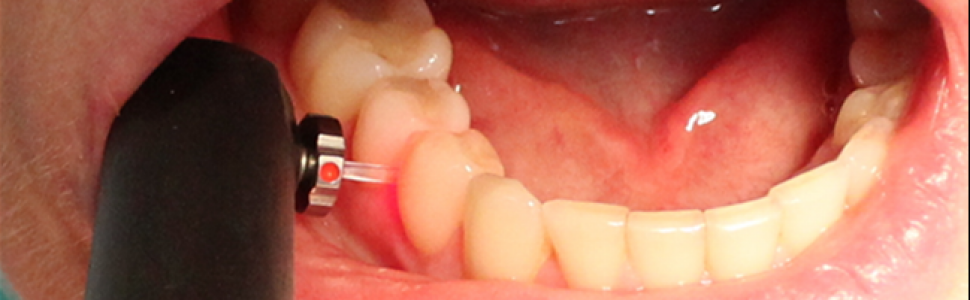

Należy pamiętać, że powierzchnia zęba powinna być przed badaniem diagnostycznym osuszona (w dalszej kolejności oczyszczona), a narzędziem zalecanym do badania dotykowego struktury tkanek zęba jest sonda WHO 621, małe upychadło kulkowe lub ekskawator (10). Do takiego badania należy zastosować również odpowiednie oświetlenie, pomocne może być powiększenie: lupy, kamera wewnątrzustna czy zastosowanie transiluminacji. Oceniając zmianę próchnicową, należy zwrócić uwagę na: lokalizację zmiany próchnicowej, obecność płytki nazębnej i przebarwień, stopień zaawansowania, ocenę aktywności, obecność (bądź brak) ubytku tkanek twardych. Najpowszechniej stosowanym systemem diagnostycznym w ocenie powierzchni stycznych jest badanie radiologiczne (11). Pitts i Rimmer w przeprowadzonych badaniach skorelowali przezierność zmian próchnicowych na zdjęciach radiologicznych z obecnością lub brakiem ubytku twardych tkanek. Żadna ze zmian wykazujących przezierność w połowie zewnętrznej grubości szkliwa nie wykazywała ubytku dostrzegalnego w badaniu klinicznym. Przezierność widoczna w połowie wewnętrznej grubości zębiny korelowała dodatnio z obecnością ubytku w 100% zbadanych zębów stałych i w 48% zębów mlecznych (12). Dodatkowymi często stosowanymi metodami, które mogą być wykorzystane w diagnostyce tego typu zmian, są metody oparte na zjawisku fluorescencji (DIAGNOdent pen, KaVo) (ryc. 3) i metody optyczne wykorzystujące wiązkę światła przechodzącą przez tkanki zęba (transiluminacja, FOTI, DIFOTI) (13).

Ryc. 3. Urządzenie DIAGNOdent pen z końcówką do oceny powierzchni stycznych.